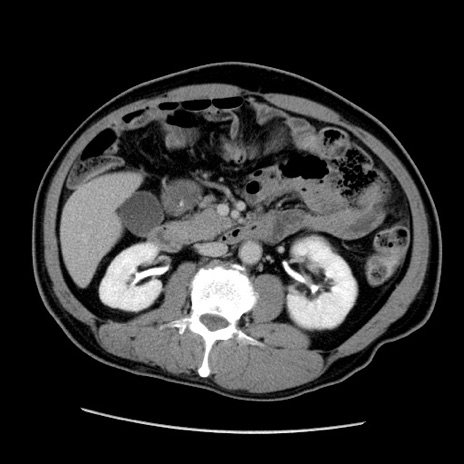

症例22(横断像)

【症例】50歳代男性

【主訴】腹痛

【現病歴】AVMからの被殻出血のため回復期リハ病棟入院中。 本日午後3時頃急に下腹部痛が出現した。

【既往歴】AVM、被殻出血、虫垂炎、高血圧

【身体所見】意識晴明、左半身不全麻痺、会話の理解は良好、36.5°C、腹部:膨隆、全体に板状硬、下腹部正中に圧痛点あり、反跳痛-、筋性防御不明、右下腹部にope scar

【データ】WBC 9400、CRP 0.06